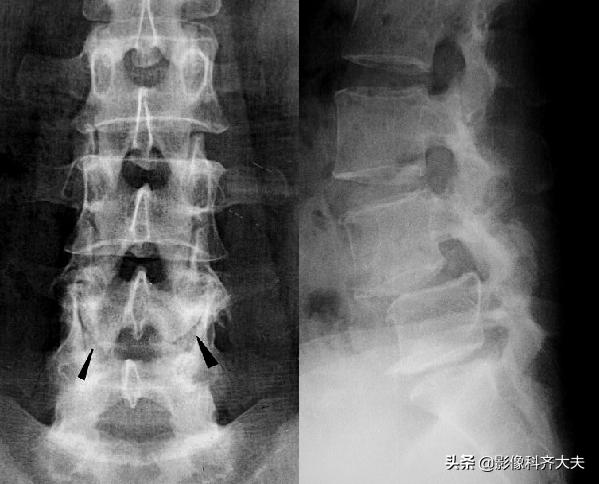

上下关节突间的椎板,称为椎弓峡部,此处骨折常发生在腰4或腰5,因身体重力向前分力作用,可使椎体向前滑脱。椎弓峡部骨折,以脊柱斜位X线片显示清楚。

腰椎正位示腰4上下关节突间斜行骨折线,腰椎侧位片示腰4前滑脱(Ⅱ度)

双斜位显示椎弓峡部骨折线影